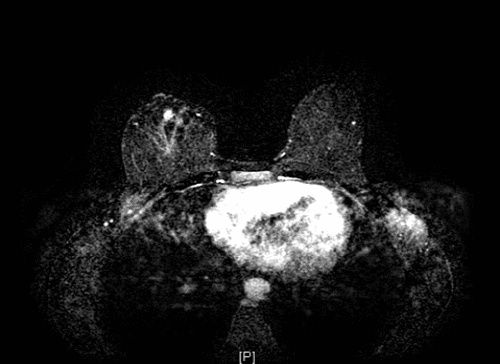

The patient was referred to a tertiary academic medical center for further management. A breast MRI was suggestive of residual disease (Figure 2), and a CT of the chest was negative for distant metastases. After a review of her case at the institution's multidisciplinary sarcoma tumor board, the consensus was to pursue definitive surgical resection with no adjuvant therapies. She underwent completion mastectomy, which demonstrated 1 cm of residual disease adjacent to the prior surgical site (Figure 3) and widely negative margins (closest > 1 cm). Interval surveillance imaging and breast/chest wall exams remained negative until two years postoperatively. While undergoing evaluation for breast reconstruction, she was noted to have an enlarging left pleural nodule and subsequently underwent wedge resection—pathology was consistent with metastatic angiosarcoma. Given this isolated recurrence on imaging, the multidisciplinary recommendation was to continue surveillance imaging, which has remained negative to date.

Figure 2. Breast MRI Demonstrating 1 cm of Enhancement Adjacent to Surgical Cavity in Right Breast, Favored Being Residual Angiosarcoma. Published with Permission

A) Axial cut of right breast

B) sagittal cut of right breast